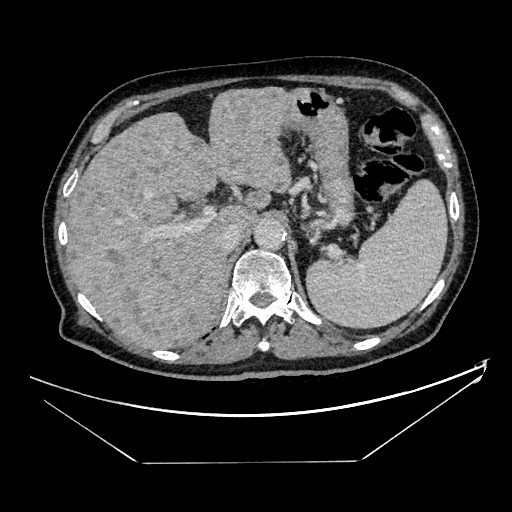

Se realiza analítica con perfil hepático: GOT 100, GPT 55, GGT 454 y FA 218 con proteína C Reactiva 146 y Lactato deshidrogenasa 1.227; por lo que se realiza ecografía clínica a pie de cama con hallazgo de múltiples imágenes hipoecoicas en parénquima hepático.

Se cursó ingreso ante el diagnóstico del paciente con posterior estudio de las imágenes hepáticas con resultado de neoplasia pancreática con incontables metástasis hepáticas.